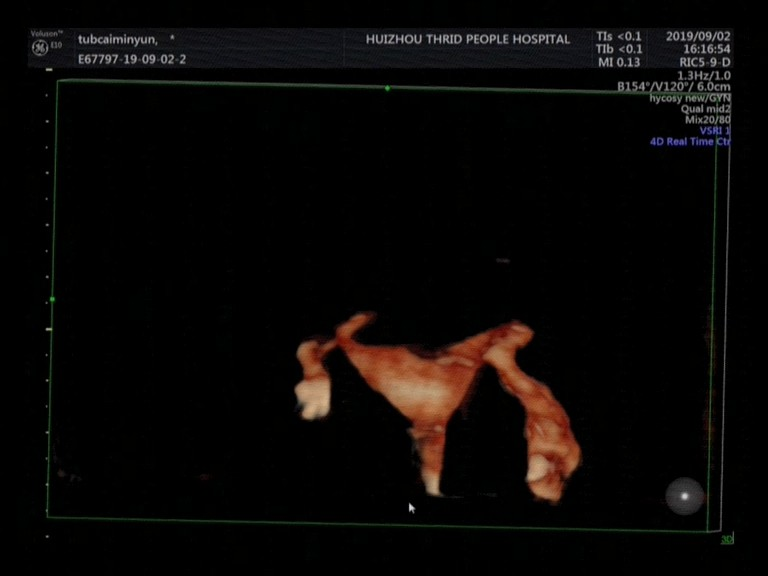

子宮輸卵管超聲造影具有實時、安全、無創(chuàng)、無放射性損傷的優(yōu)點,尤其是利用三維子宮輸卵管造影,可清晰顯示出輸卵管的空間立體走形,及造影劑在宮腔、輸卵管的顯影過程的實時動態(tài),幫助準確評估輸卵管通暢程度。

雙側輸卵管通暢